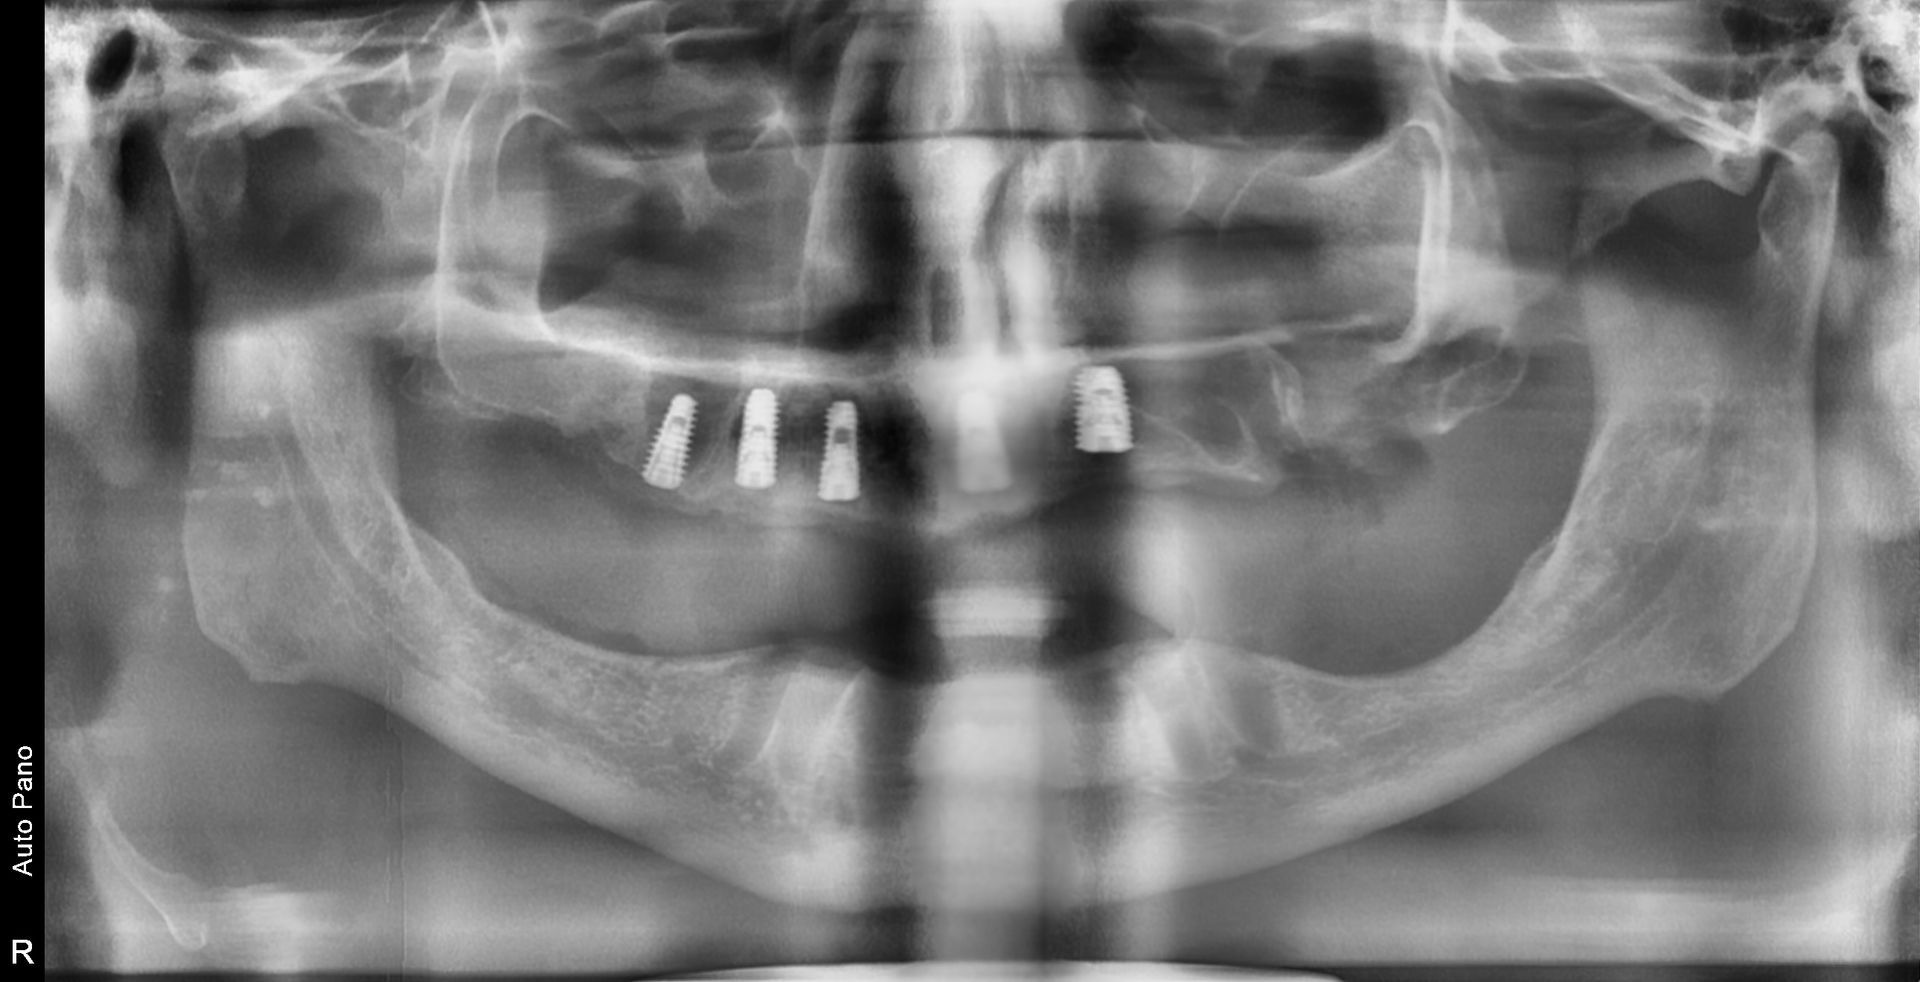

The panoramic radiograph confirmed a fully edentulous state in both the maxilla and mandible,

with all teeth already extracted.

This image shows multiple implants placed in the maxilla.

Because the maxillary bone is relatively soft, achieving strong primary stability

at the time of placement is especially important.

Bone grafting was performed where necessary, and adequate healing

time was allowed afterward to ensure successful osseointegration.